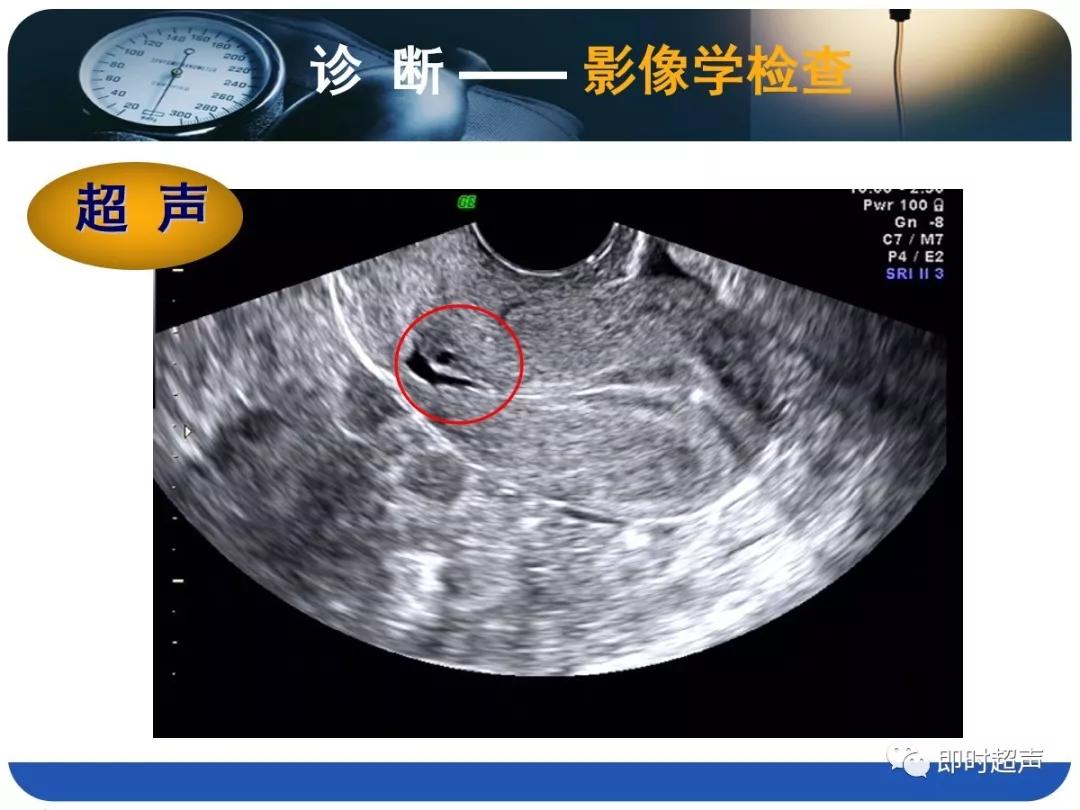

- 诊断主要依据病史(手术史)、临床表现(异常阴道流血)、检查结果(B超、HSG、宫腔镜等)综合判断。

- B超的特征性改变为:子宫下段或子宫峡部、宫颈管上段原剖宫产切口疤痕处肌层不连续,肌层内不规则液性暗区。